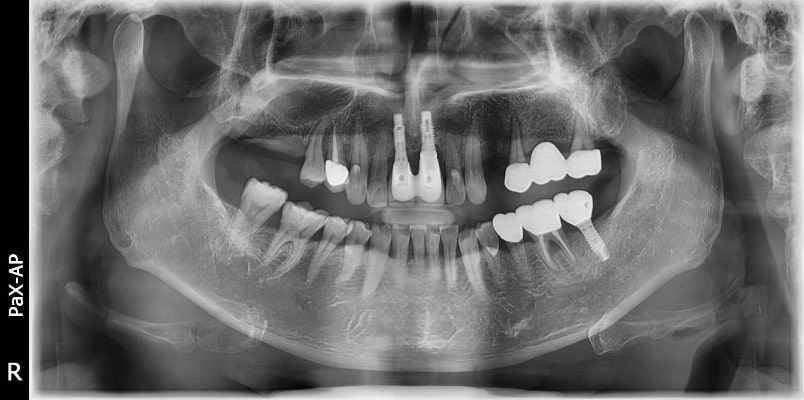

El innovador FOV proporciona un volumen en forma de arco que muestra una vista más amplia de la dentición en comparación con otros dispositivos del mismo FOV.

Normalmente, una imagen de 10x8.5 muestra el diente No.8. Sin embargo, cuando los terceros molares están tumbados sobre su lado hay una gran posibilidad de que el diente se corte de la imagen.

El “volumen en forma de arco” elimina esta posibilidad y muestra el área de dentición oculto.